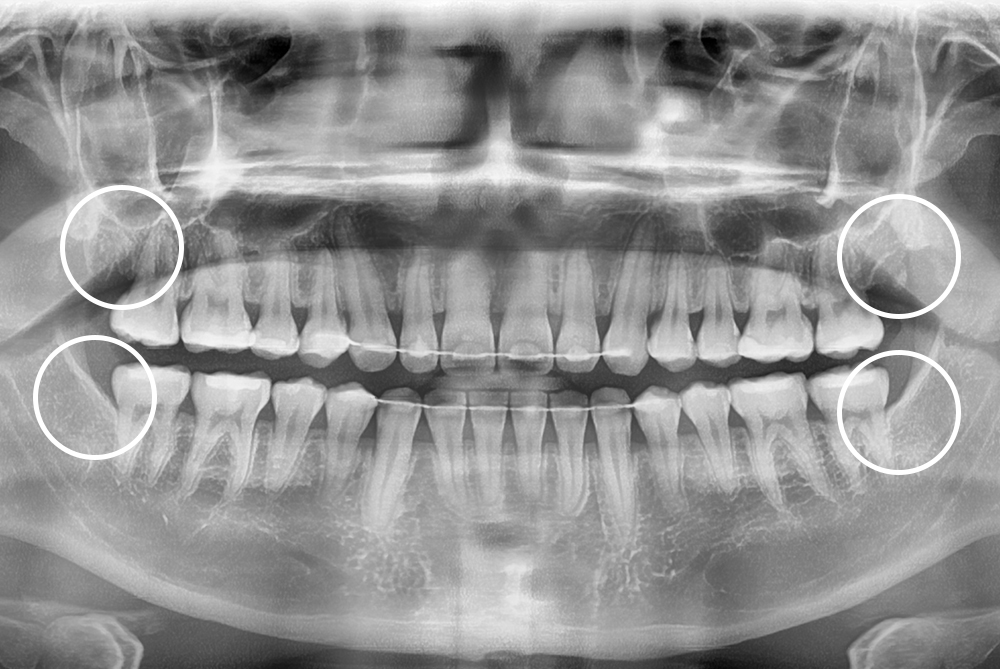

[사랑니] 매복 사랑니 발치

치료후 : 2022-04-04

세종치과는 구강악안면외과학 박사이신 원장님이 발치하는 치과입니다.